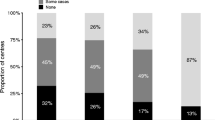

In 2013, there were 2686 infant deaths in England and Wales [26]; of these, approximately 1000 will have presented as a sudden, unexpected death (SUDI). Due to the nature of these cases, they usually require investigation through HM Coroner (in England, Wales and Northern Ireland) or the Procurator Fiscal (Scotland). SUDI presentations represent the commonest group of infant deaths undergoing autopsy examination [27] but despite a relatively high throughput of cases, SUDI remains poorly understood, and investigation of SUDI deaths are a challenging area for medical practitioners. The majority of investigations within the Coronial / Fiscal system require a cause of death to be established to a standard of proof equating to ‘on the balance of probability’, rather than ‘beyond reasonable doubt / so as to be sure’. Even so, the majority of SUDI deaths remain unexplained [28]. Of the cases where a cause of death may be identified, the potential underlying may be subtle, thus requiring a rigorous approach to the investigation. A keen understanding of the rapid physiological changes that occur during the first year of life is therefore essential when considering SUDI cases. The investigative strategy recommended by the Royal College of Pathologists is extensive [29] but largely based on expert opinion, rather than evidence. An updated guideline is expected to be published in 2016. A recent systematic review evaluating SUDI investigation strategies described the need for mandatory investigation of SUDI cases, ideally through specialist centers, that can provide strong leadership and integrate with Coronial services [30].

Some presentations of SUDI will be attributable to natural causes (undiagnosed infections, congenital malformations), whilst some will occur in unnatural circumstances, including accidents, and some within the context of inflicted injury [28]. Of the SUDI cases that remain unexplained, some will occur in association with well-described risk-factors, such as co-sleeping, prone sleeping, soft-bedding, parental smoking or drug use, and socio-economic deprivation [30–33] though a definitive cause of death may elude the investigative team. A proportion of unexplained SUDI cases may be classified as SIDS (Sudden Infant Death Syndrome) if the cause and mechanism of death cannot be explained following completion of all investigations and the death occurred during normal sleep. SIDS remains a diagnosis of exclusion, and in practical terms is likely to represent a heterogeneous mixture of cases with complex, multifactorial causes that current gold standard investigations cannot adequately detect or classify [26, 34].